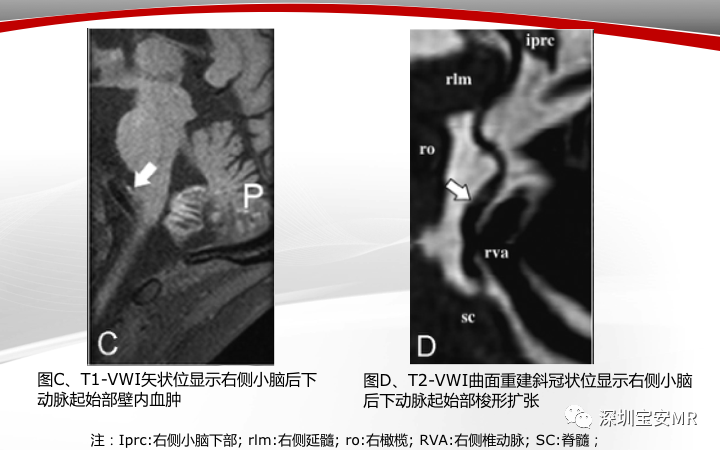

【病例】小脑后下动脉夹层1例MR